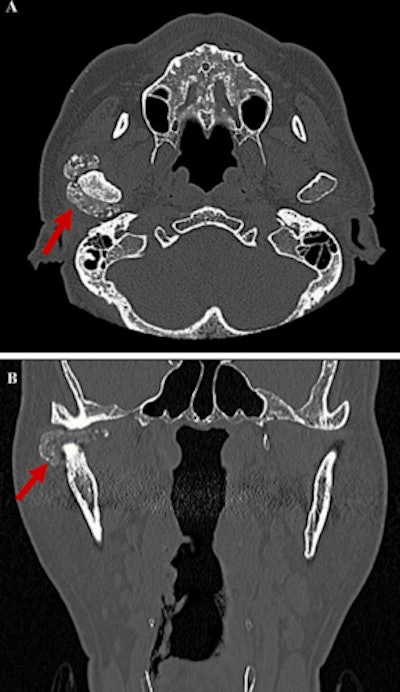

Dental x-rays showed horizontal bone resorption in the upper and lower jaws and extensive calcificationlike opacities in the right TMJ while magnetic resonance imaging (MRI) showed the dilation of the upper and lower joint spaces with differing levels of hypointensity. However, there was no observable disc dislocation in the joint on the right side, and the left side showed nothing abnormal, they wrote.

The man underwent a computed tomography scan that revealed an area of hard tissue that measured 38 mm, multiple rice-grain opacities around the right mandibular condyle, and osteosclerosis of the right articular head with no observable bone resorption, the authors wrote.

Based on the imaging and clinical features, the differential diagnosis was a tumor or a tumorlike disease. To get a definitive diagnosis, a biopsy was done. Upon opening the superior articular space, a mass covered with a fibrous capsule was seen. The mass, which was surrounding the mandibular condyle and had numerous white, cartilagelike hard tissues and chalklike soft tissues of mixed sizes, was removed and sent to the lab for analysis. Results showed that the mass was formed by aggregates of basophilic crystal deposits surrounded by a giant cell reaction, the report's authors wrote.

Since the patient had no history of trauma and imaging revealed joint effusion with multiple calcified loose bodies in a tumorlike lesion with a well-defined border surrounding the lower jaw condyle of the right TMJ and the loose bodies were confirmed by histopathology, the patient was diagnosed with calcium pyrophosphate crystal deposition and synovial chondromatosis, according to the case report.